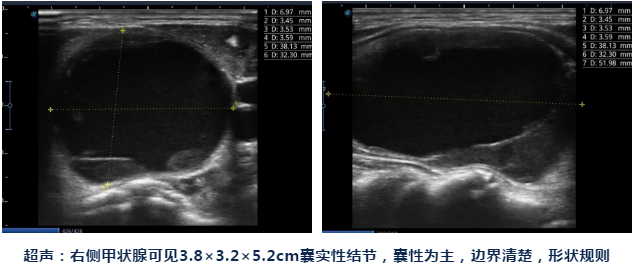

谁知脖子上的肿块越来越明显,现在感觉已长到有鸡蛋大小,轻轻一碰就疼得厉害,这让王女士再也坐不住了,决定赶紧到附近的北京燕化医院检查看看。到了燕化医院,做了颈部超声检查一看,原来是右侧甲状腺长了一个5厘米多的结节,医生建议手术切除。

带着种种担心和疑虑,王女士慕名找到了燕化医院肿瘤微创介入科陈力强主任。陈主任给王女士做完甲状腺超声检查后告诉她,她的甲状腺结节是囊性为主,应该是良性可能性更大,可以做一个超声引导下甲状腺结节穿刺活检进一步明确。